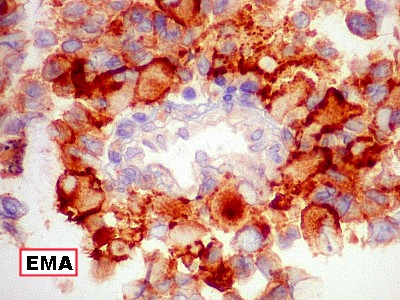

EMA.

Antígeno epitelial de membrana. Também indica diferenciação

epitelial. |

| EMA.

Positiva no tumor, negativa em vasos proliferados. |

Positiva no epêndima do III ventrículo, inclusive em células

ciliadas. |